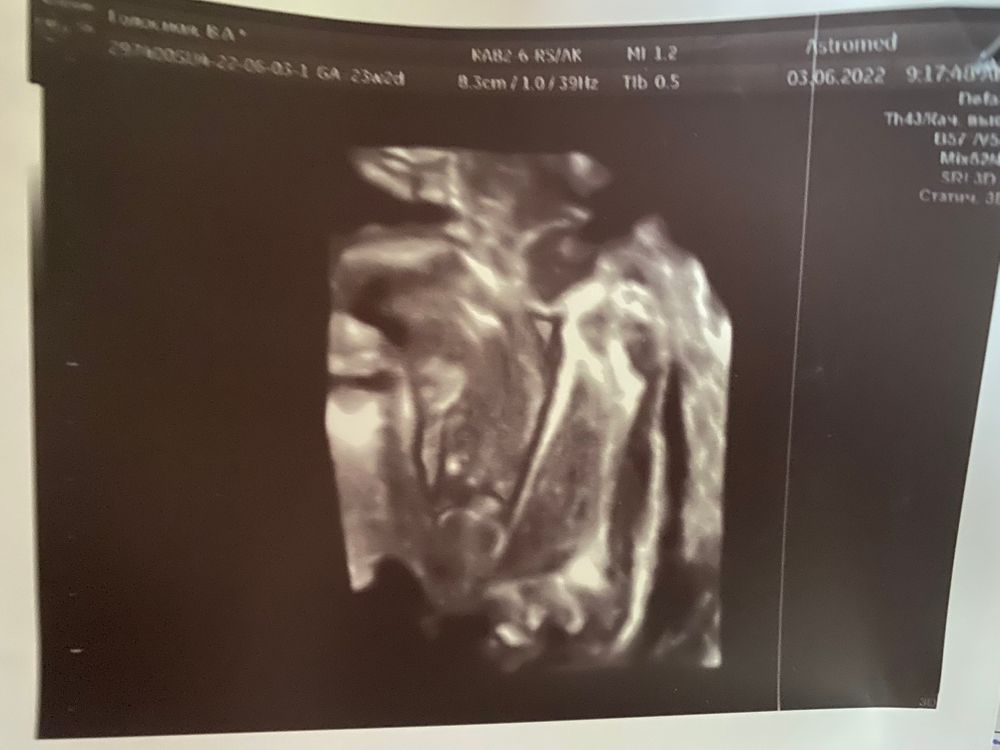

Чуть ракурс бы другой ,мне тоже на узи смотрели снизу и так на девочку был похож ,на 23 недели уже показали и писюху точно .Вид снизу как у вас ,будто пирожок был .Сходите платно на узи ,можно даже чисто на определение пола )так и называется услуга ) Изображение